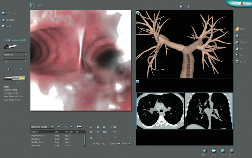

The Simbionix BRONCH Mentor combines the virtual with the physical to create the ultimate training solution for flexible bronchoscopy, using an authentic scope with tactile feedback in a true-to-life physical environment.

The Simbionix BRONCH Mentor offers the most comprehensive environment while supporting gradual and controlled complexity and simultaneity.

The Simbionix BRONCH Mentor provides an optimal learning environment for motor, cognitive and coordinative skills acquisition. Full clinical procedures of diagnostic and therapeutic nature are simulated comprehensively.

The Simbionix BRONCH Mentor offers a variety of virtual patients exhibiting real life patient environment and behaviour.

DIAGNOSTIC BRONCHOSCOPY MODULE:

This module includes different patient scenarios each constitutes an entire clinical environment in which the user can perform endobronchial and transbronchial tissue sampling using biopsy forceps, cytology brush, aspiration needle and BAL.

All cases incorporate a complete patient management environment with moderate sedation, altering consciousness, vital signs monitoring, hemodynamic complications and more.

This clinical environment offers multiple educational aids to optimize the learning process, or it can be restricted to data available during a real procedure.

All of the above are simulated in a reactive manner, enhancing the bronchoscopic simulation to the full spectrum of the actual procedure.